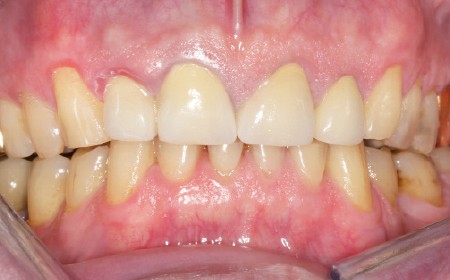

Bruxisme : net avec attrition antérieure marquée en particulier en regard des coiffes céramiques.

Occlusion : décentrage gauche, création d’une légère béance antérieure probable conséquence

de l’atteinte de l’ATM gauche.